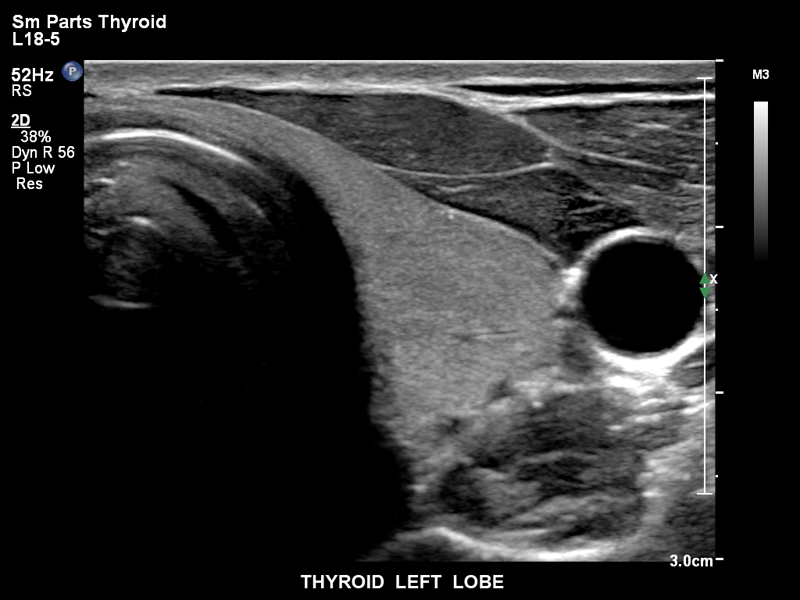

Щитовидная железа, левая доля, L18-5